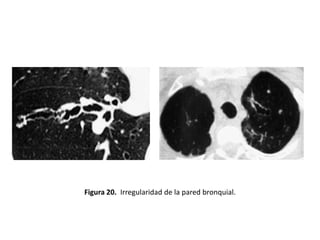

• Otros hallazgos demostrables mediante un estudio

con TAC y que pueden constituir signos indirectos de

BQ serían: (figuras 19-22).

– Enfisema

– Irregularidad de la pared bronquial

– Atelectasias

– Pérdida de volumen o áreas de consolidación

Figura 20. Irregularidad de la pared bronquial.

• Varicosas:

– Los bronquios presentan dilataciones irregulares

– Alternando zonas de dilatación con zonas de

constricción localizadas y terminación bulbosa

– Aspecto arrosariado o en “ristra de perlas” cuando

el bronquio afectado transcurre horizontal al

plano de corte (Figura 20 y 24).